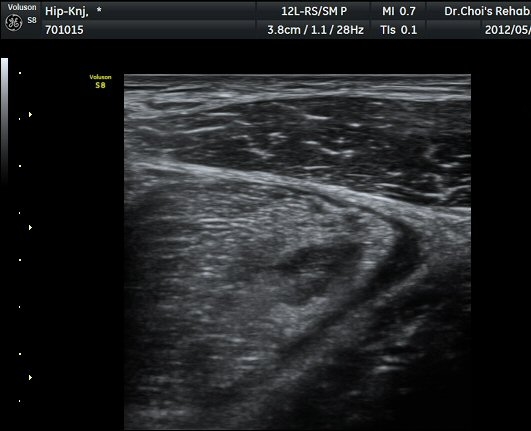

ŽÃËÀÚ¸¦ ¾Æ·¡·Î À̵¿ÇÏ´Ï ´ëÅðÁ÷±Ù³»¿¡ Àú¿¡ÄÚ º¯º¯ÀÌ °üÂûµÈ´Ù(±×¸² 2, 3).